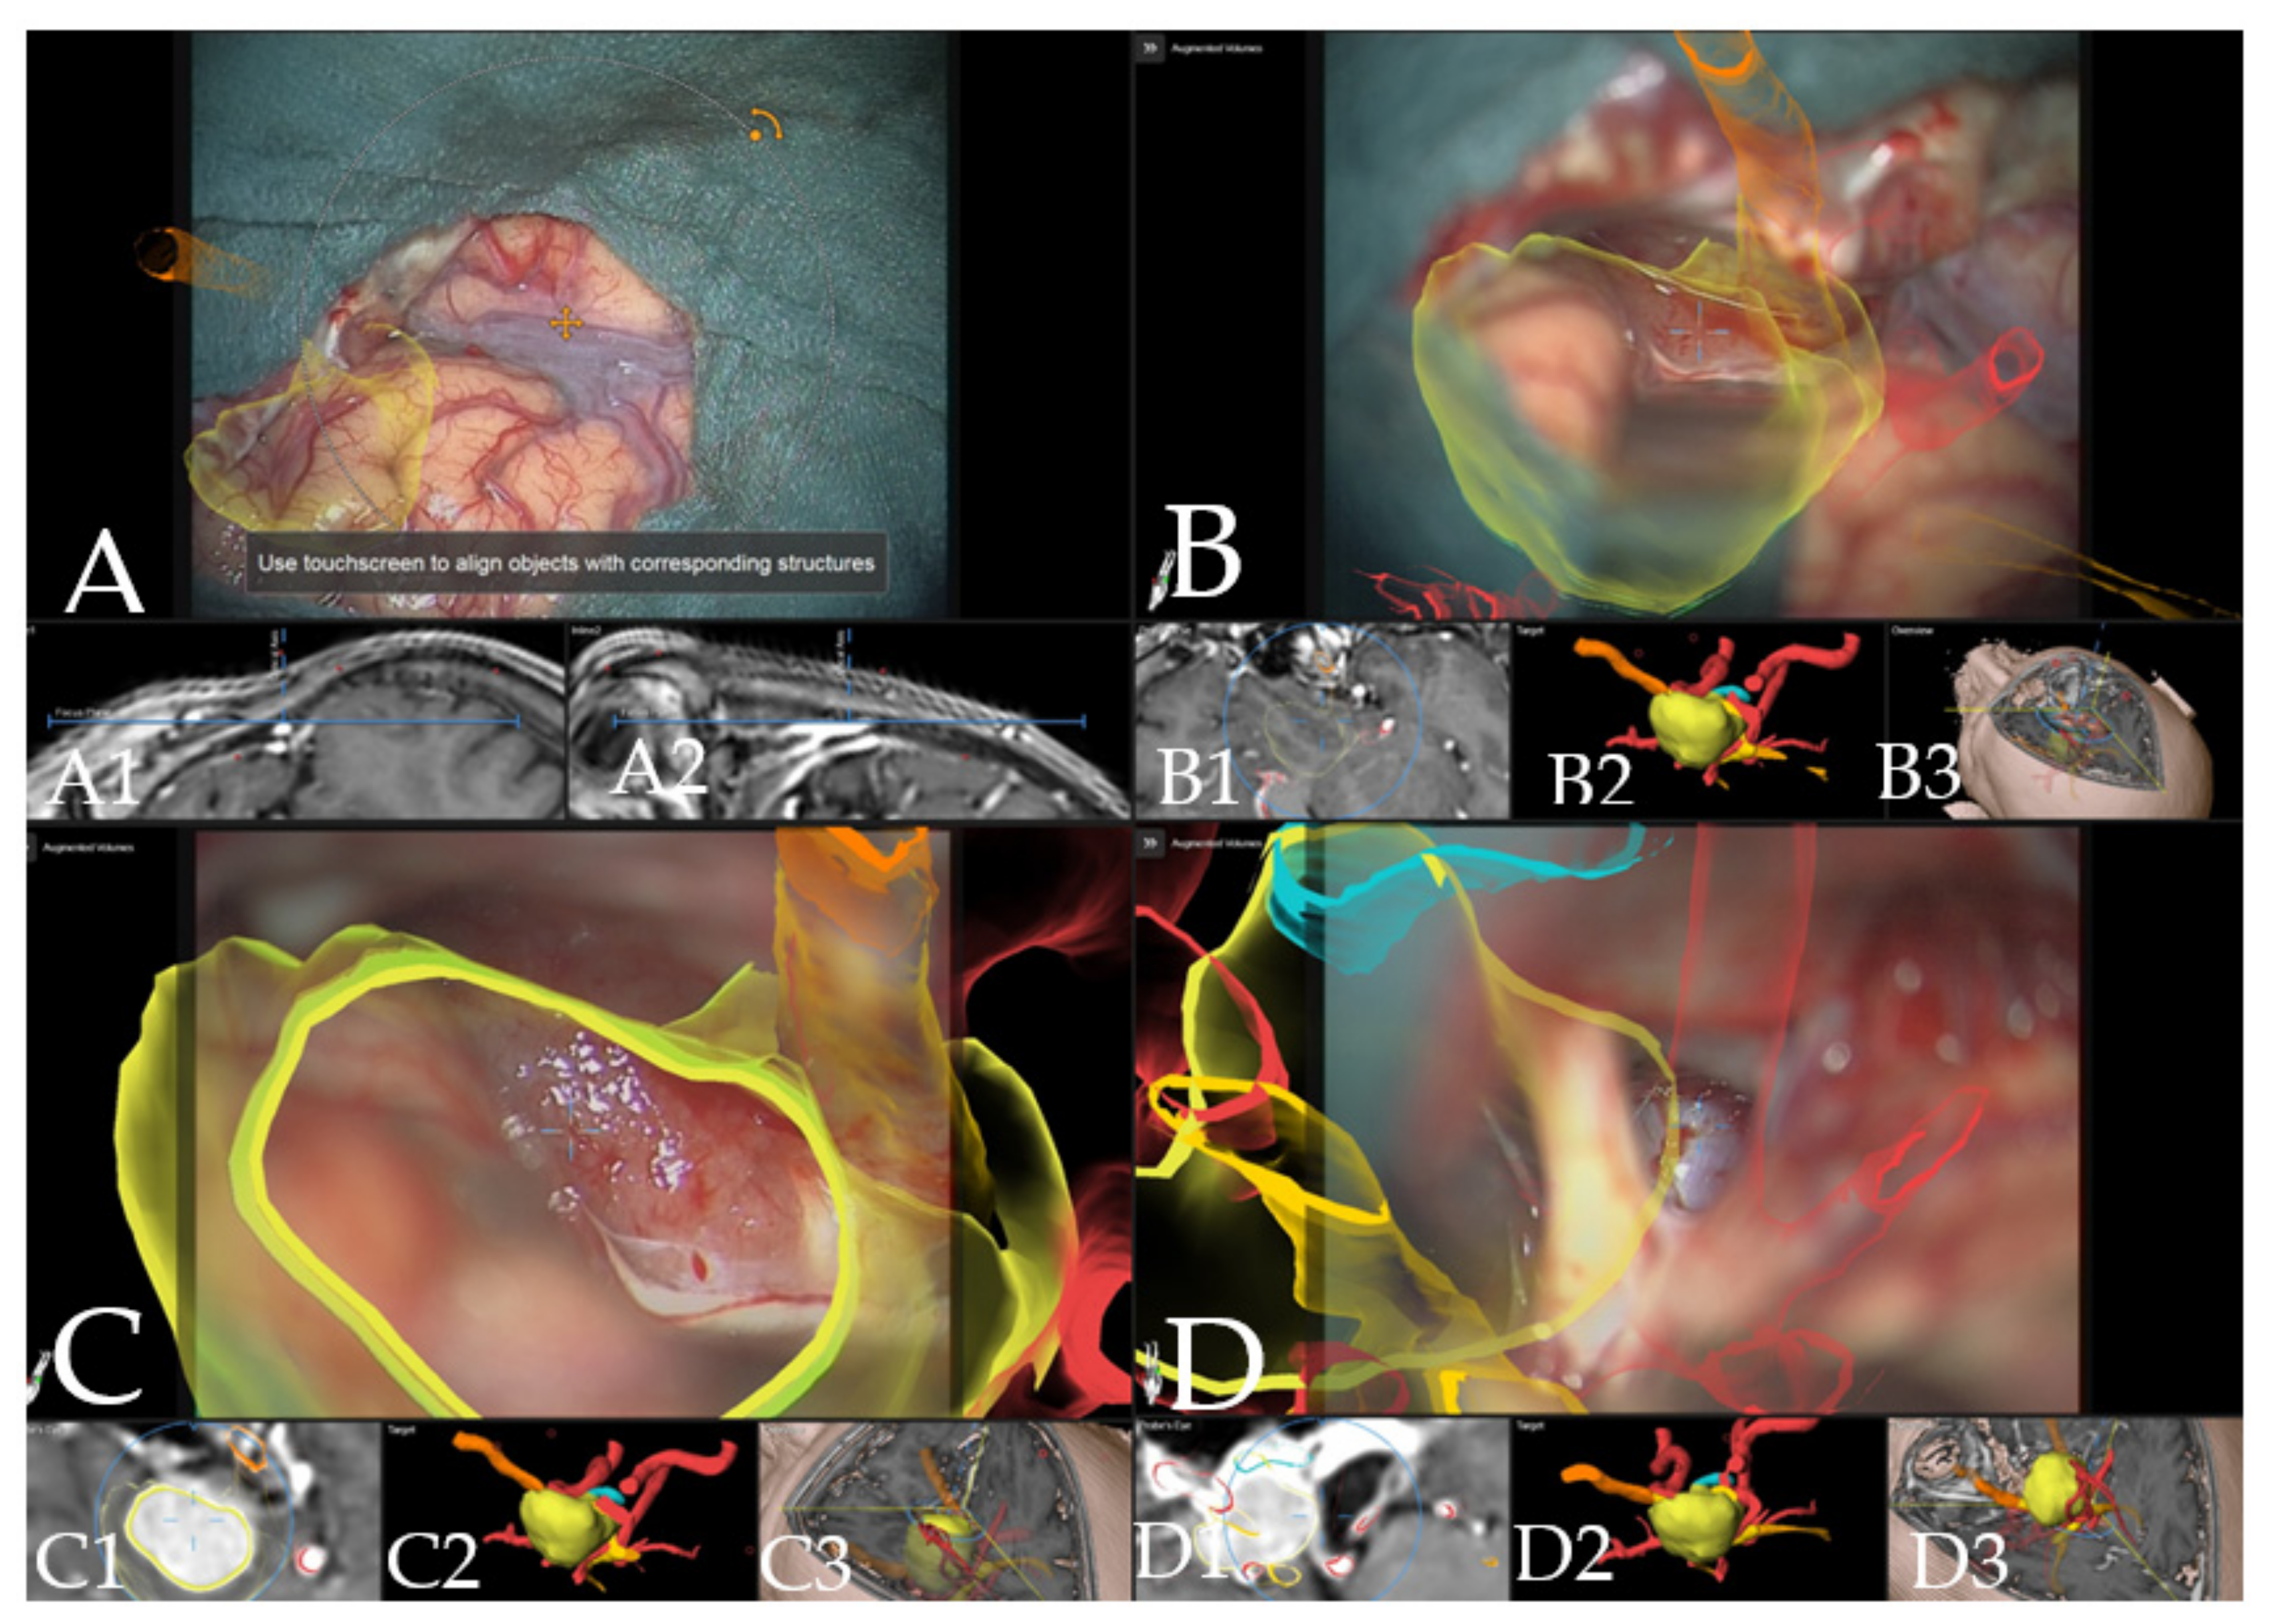

Illustrative Cases